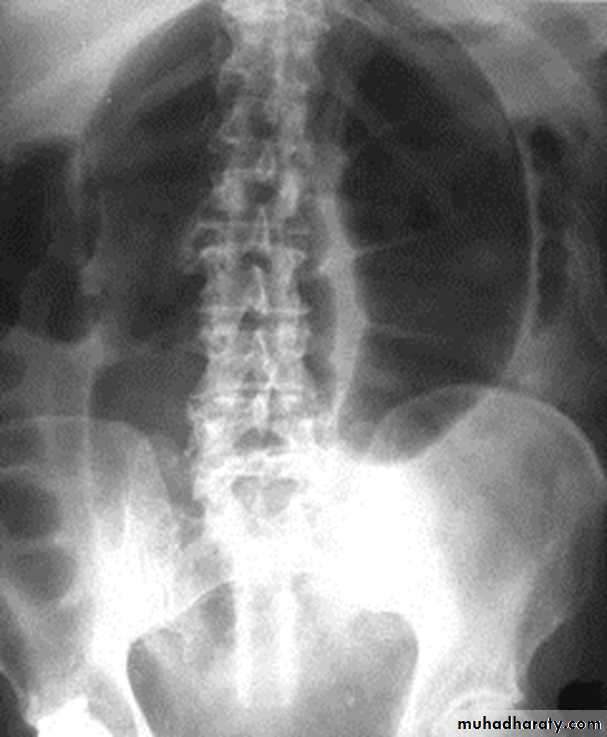

Slide 31- What are the finding in this plane X ray?2- What endocrine disease can cause such condition?